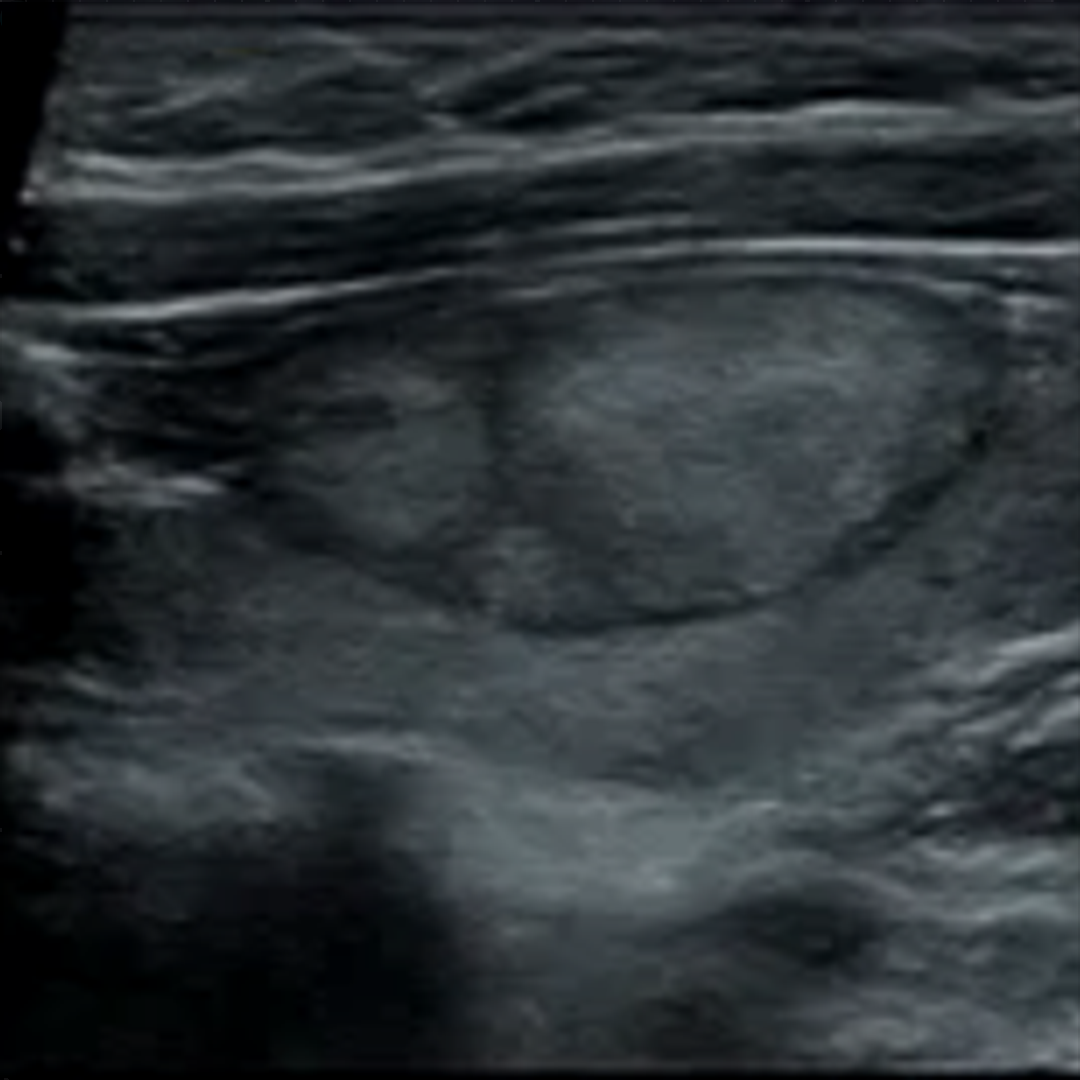

单发结节和多结节超声图像